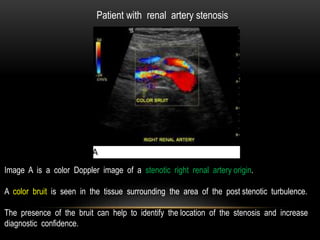

Patient with renal artery stenosis

Image A is a color Doppler image of a stenotic right renal artery origin.

A color bruit is seen in the tissue surrounding the area of the post stenotic turbulence.

The presence of the bruit can help to identify the location of the stenosis and increase

diagnostic confidence.